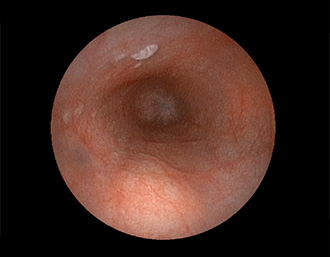

②胃潰瘍(Stage H1)・治療後18日目

胃角部小弯の潰瘍。潰瘍辺縁は平滑で、白苔は部分的に薄い箇所もあり、全周性に再生上皮を認める。